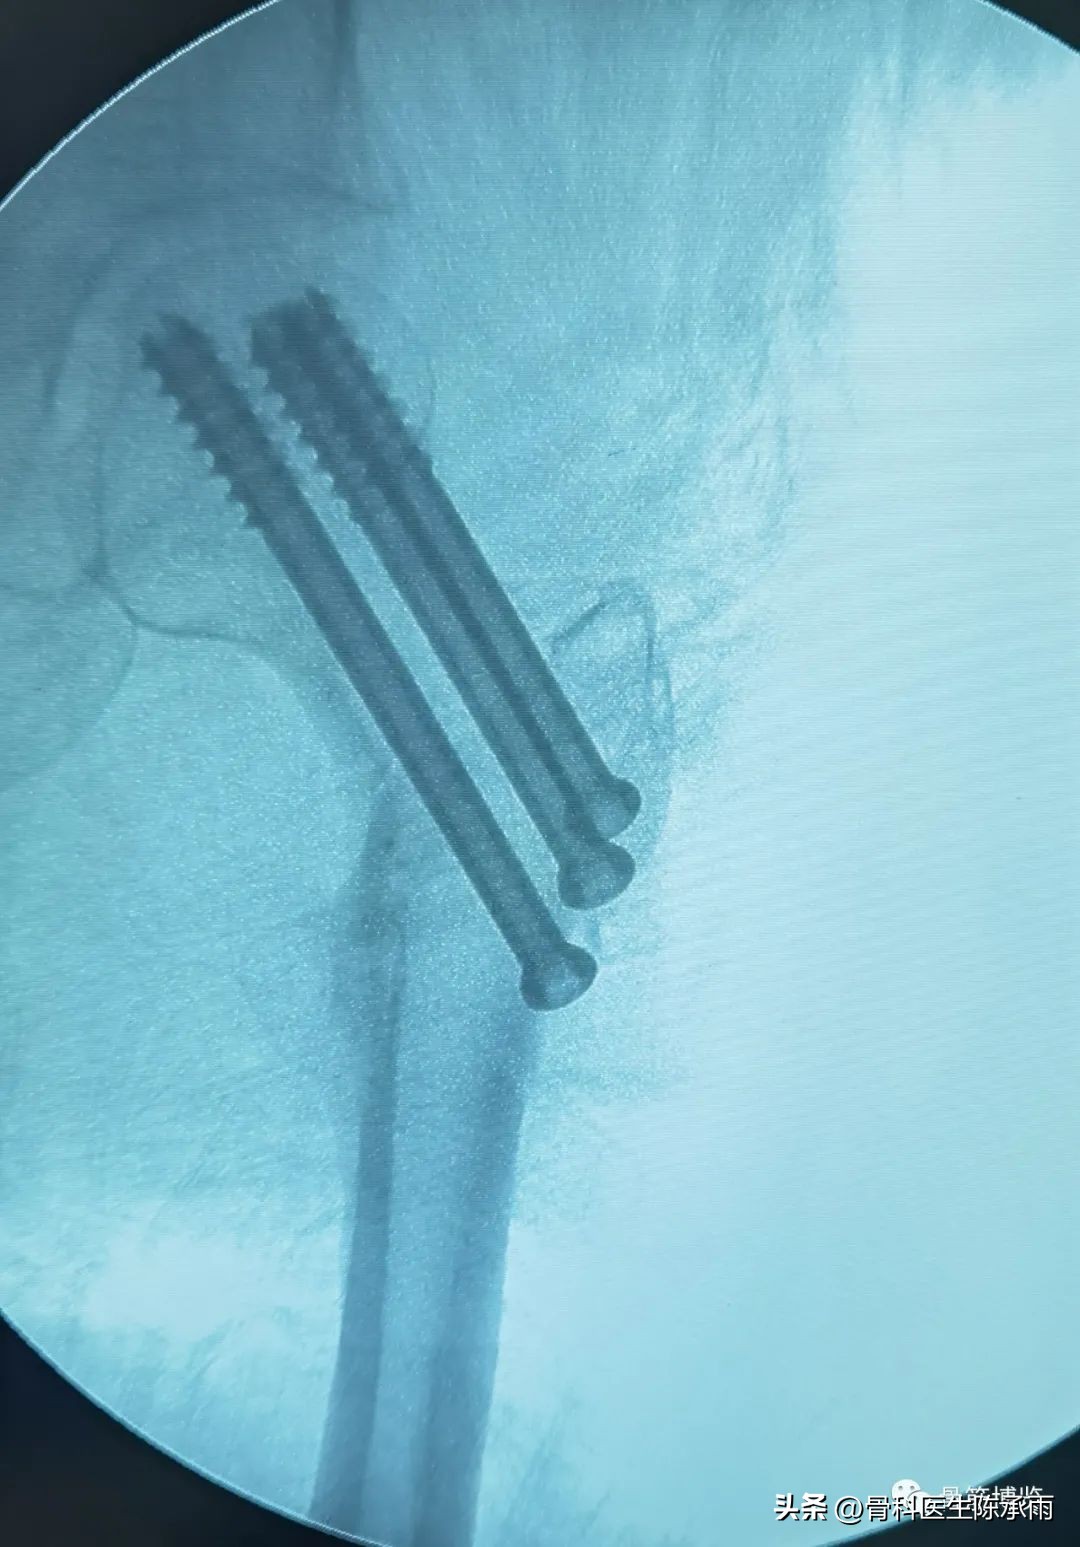

常规股骨颈骨折相对简单

术后复查